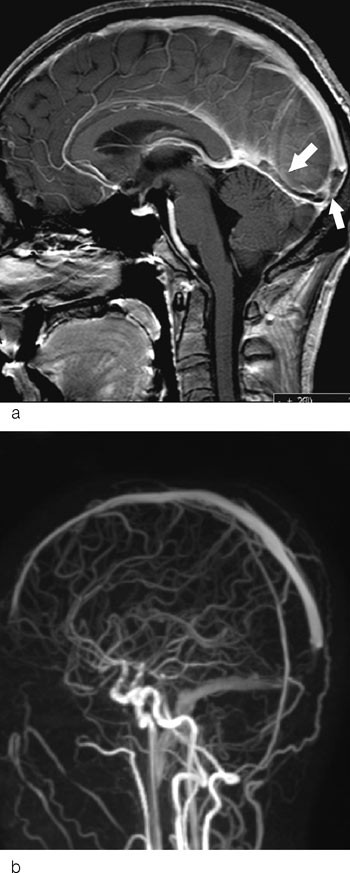

Konvensjonell angiografi med digital subtraksjonsteknikk (DSA) har tidligere vært ansett som gullstandard for påvisning av sinusvenetrombose (19). Siden dette er en invasiv teknikk som ikke gir informasjon om forandringer i hjerneparenkymet, er den i dag lite brukt ved denne problemstillingen (14). MR er den mest brukte bildeteknikk ved klinisk mistanke om cerebral venetrombose (18). I motsetning til DSA-metoden er den ikke-invasiv, og den viser bedre enn CT både selve tromben og hjerneparenkymforandringer sekundært til tromben. Ved spørsmål om cerebral venetrombose vil man i tillegg til standard bildeserier også gjøre venøs MR-angiografi. Diffusjonsvektede sekvenser vil være nyttig for å påvise utvikling av venøse infarkter. Såkalte hemosekvenser (gradientekko) er følsomme for blodprodukter og er velegnet for å påvise hemoragiske områder i venøse infarkter.

Et typisk bildediagnostisk tegn ved cerebral venetrombose er en fyllingsdefekt i venesinus (fig 1). Disse fyllingsdefektene er hypertette på CT. I sinus sagittalis superior vil fyllingsdefekten ofte ha en trekantet form. På MR vil signalet i tromben variere med alderen (fig 2). Trombene kan også strekke seg retrograd fra venesinus og inn i de kortikale venene. Sekundære forandringer til sinusvenetrombose er hjerneødem og venøse infarkter, typisk beliggende subkortikalt og kortikalt (fig 3). I motsetning til arterielle infarkter vil de venøse ikke følge forsyningsområdene for de store cerebrale arteriene, en annen forskjell er større ødem ved venøse infarkter (18). Venøse infarkter vil ofte være hemoragiske, og på såkalte hemosekvensbilder vil man se blodproduktene som områder med lavt signal.